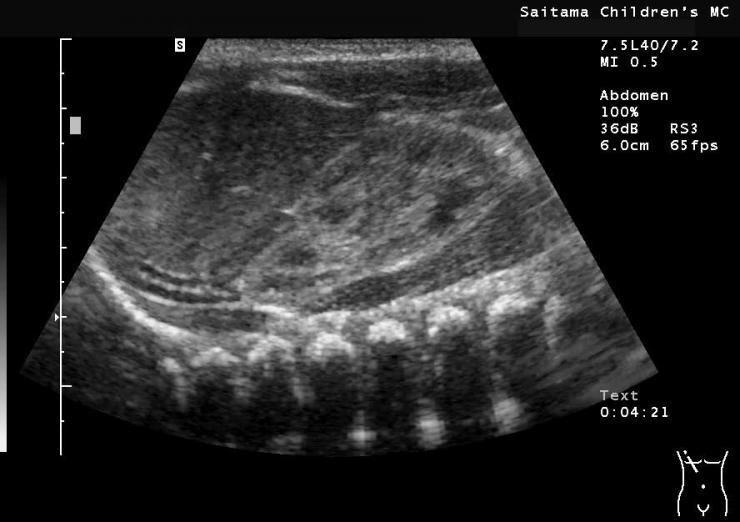

超音波検査のご紹介

超音波検査は、人間には聞こえないほどの高い周波数の音を使って体の断面を見る検査です。体の中に出された超音波は、骨や空気、臓器などに反射して山びこのように戻ってきます。骨や空気からは大きな音で、臓器などからは小さな音で戻ります。また、距離の近いものに反射すると早く、遠いものからは遅く戻ってきます。この音の大きさと時間の差を利用して画像にしています。超音波検査では、体の中を動画として見ることができるため、臓器の大きさや形態だけでなく、動きや血液の流れなどもリアルタイムで見ることができます。また、放射線による被曝も無く、患児の苦痛も少ない検査と言えます。しかし低年齢児にとっては、比較的検査時間が長く(平均15分程度)、室内の照明を暗くするため不安でもあります。そのため、アニメーションのビデオを見せたり、乳幼児には母体から発生する心音と同じような音を出す人形を傍に置いて、検査がスムーズに進行するよう努力しています。とは言ってもお子さんに一番安心感を与えられるのは、ご家族の方が傍にいてあげる事ですので、検査時の同室にご協力をお願いしています。